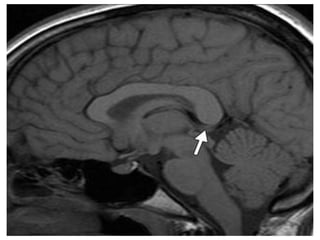

a)Sagittal T1 weighted MR

image shows an

heterogeneous pineal region

mass with foci of T1

shortening due to

hemorrhage , note the

associated hydrocephalus

b)Axial postcontrast T1-

weighted MR image shows

that the pineal region mass

also has an heterogeneous

enhancement with foci of

necrosis/cyst , involvement of

the tectal plate and both

thalami are also present (not

shown) , evaluation of serum

oncoproteins demonstrated

high level of b-hCG , biopsy of

the lesion revealed that it

corresponds to

Choriocarcinoma

a)Sagittal T1 weightedMR image shows an heterogeneous pineal region mass with foci of T1 shortening due to hemorrhage , note the associated hydrocephalus b)Axial postcontrast T1- weighted MR image shows that the pineal region mass also has an heterogeneous enhancement with foci of necrosis/cyst , involvement of the tectal plate and both thalami are also present (not shown) , evaluation of serum oncoproteins demonstrated high level of b-hCG , biopsy of the lesion revealed that it corresponds to Choriocarcinoma